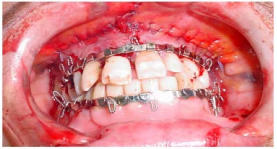

Quanto ao tratamento de fraturas faciais, o material e o

instrumental ilustrados na imagem abaixo são utilizados

para:

A imagem abaixo ilustra a técnica de bloqueio maxilomandibular com barras de Erich, que é utilizada no

tratamento de fraturas da face com o objetivo de: